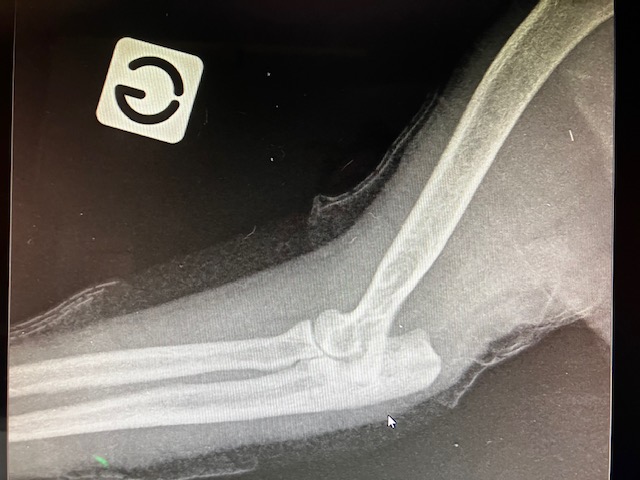

Un suivi radiologique est mis en place, avec un cliché toutes les 3 semaines. Cette fois, le montage tient correctement, on voit la cicatrisation osseuse progresser, le trait de fracture radio-transparent disparait.

La cicatrisation osseuse étant satisfaisante, il faut maintenant retirer le matériel chirurgical, c’est préférable pour améliorer le confort de l’animal,la broche pouvant générer une douleur au coude.

Résultat final : La fracture est guérie. Le coude est tout de même « ankylosé » au bout de quelques mois, mais la ré-éducation va se faire progressivement avec la reprise d’activité.